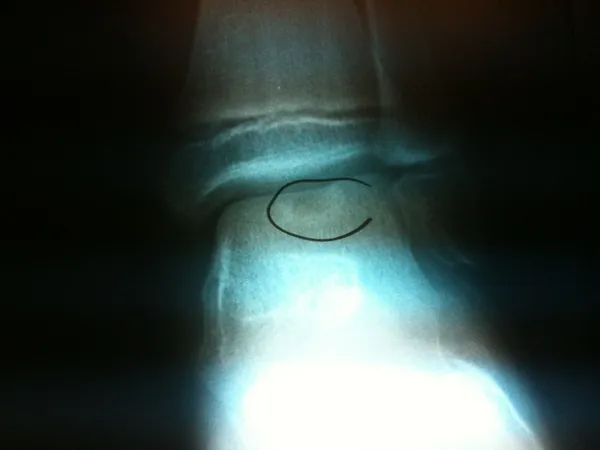

Intraop series of pics of a large osteochondral fracture on the shoulder of the talus in a teenage soccer player.

The osteochondral fracture can be seen and it is loose. We are measuring the size on the last 2 pics.